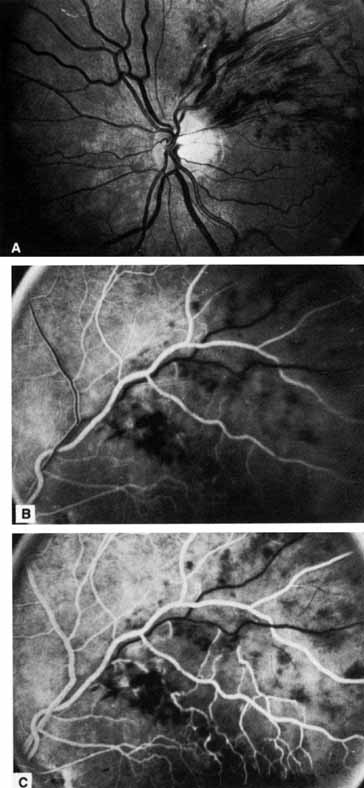

Fig. 1 A. “Blood and thunder” appearance of a central retinal vein occlusion. B. Intravenous fluorescein angiogram shows this occlusion is primarily ischemic or nonperfused. The fact that there is more nonperfusion in the inferior half of the fundus compared with the superior half is unusual.

Coats55 may have been the first to suggest that patients with central retinal vein occlusion fall into two groups: one with a dramatic, “blood and thunder” ophthalmoscopic appearance, loss of vision, and a poor prognosis (see Fig. 1); and the other with mild ophthalmoscopic changes, generally good visual acuity, and a relatively good prognosis (Fig. 2). Other investigators have commented on the difference in severity among central retinal vein occlusions, relying principally on the fluorescein angiogram to assess the severity of occlusion.56–59

The intravenous fluorescein angiogram pattern of an ischemic central retinal vein occlusion is usually characterized by a delayed filling time of the venous tree of the retina, capillary and venous dilation, and extensive leaking of fluorescein into the retina, particularly in the macular area and in the area adjacent to the larger venous trunks and capillary nonperfusion (see Fig. 3C and 3D; Figs. 4 and 5). Microaneurysms may not be noted at the time of initial occlusion, but are usually manifest shortly thereafter. Late-phase photographs show patchy extravascular areas of fluorescence and staining of the retinal veins. Fluorescence in the macula indicates capillary leakage and edema; this not only may account for much of the initial visual loss in the acute phase, but may also eventually result in permanent structural changes. Intravenous indocyanine green videoangiography may also be helpful in showing the arterial and venous flow alterations in this condition.322

Fig. 4 Fluorescein angiogram after moderately ischemic central retinal vein occlusion. A. Early venous phase. The capillary bed is dilated and engorged. Punctate areas of fluorescence represent microaneurysms or small areas of capillary leakage. B. Midvenous phase. There is considerable delay in venous return and an increase in and coalescence of punctate areas of extravascular fluorescence. C. Late venous phase. Fluorescence staining along the vein margins and scattered areas of capillary nonperfusion (arrow) are present.